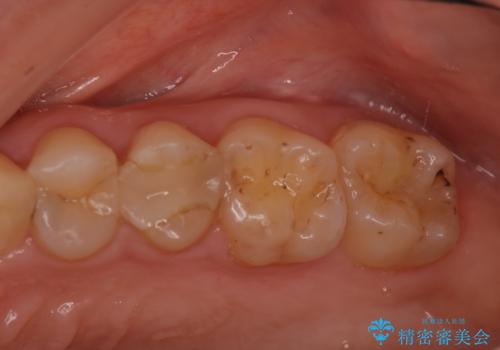

奥歯の着色が気になる セラミック治療

担当医 菊地俊介